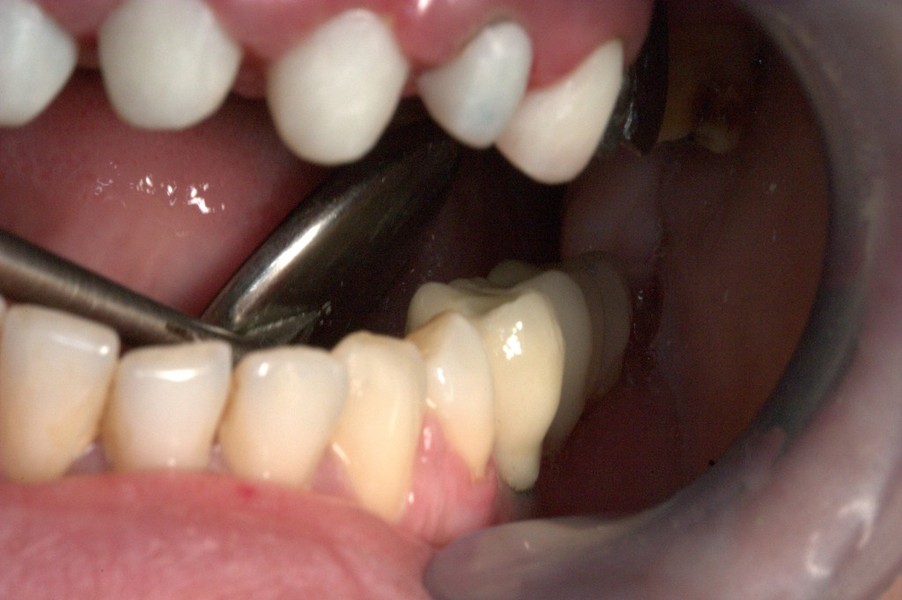

Paciente afectada de Enfermedad Periodontal Avanzada, en ambos maxilares.

En el maxilar superior, perdida ósea vertical generalizada de más de 5 mm, movilidad grado I y grado II.

En maxilar inferior , enfermedad periodontal avanzada del adulto, con perdida de inserción ósea y ligamentosade 5 mm en casi todas las piezas  a excepción de las piezas31 y 41 incisivos  inferiores, con recesisón gingival de atkins y sullivans grado 2.Con defecto vertical superior a 7 mm.

Tratamiento de la enfermedad Periodontal. Con cirugías periodontales de Widman modificado por la técnica de Ramfjiord por cuadrantes, Raspajes curetajes y alisado radicular.